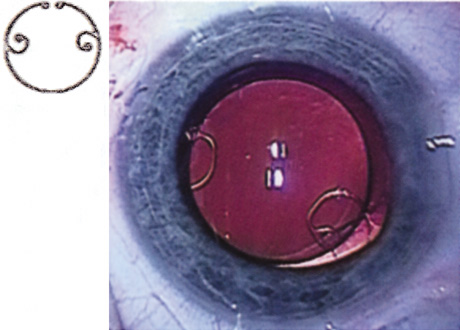

Although slit-lamp examination can give the ophthalmologist an excellent estimate of endothelial health, sometimes a formal assessment of the corneal endothelial cell density is helpful (Fig. 4). This information is most likely to be helpful in advising patients who may be at greater risk of postoperative corneal decompensation. Specifically, patients with cornea guttata, previous ocular surgery, history of blunt ocular injury,56 exfoliation syndrome,57 iridocorneal-endothelial syndromes,58 or a history of glaucoma59 are known to have reduced endothelial cell counts. Patients with a history of acute angle closure are at particular risk because each episode of elevated intraocular pressure can damage endothelial cells.60

There are qualitative and quantitative methods for endothelial cell evaluation. Cell density can be measured directly with an endothelial cell camera. The surgeon also should view the photograph and qualitatively estimate the regularity of the endothelial cell mosaic. Some instruments calculate a coefficient of variability and percent of hexagonal cells.

When an endothelial cell camera is not available, qualitative assessment of count and cell morphology can be accomplished at the slit-lamp using a technique called specular reflection.61 The ophthalmologist focuses a narrow parallelepiped on the corneal epithelium, directing the beam at the periapical cornea from a 45-degree angle. The slit beam is moved slowly from side to side until the bright corneal reflex strikes the examiner's view from the epithelial surface reflection (first Purkinje-Sanson image). On high magnification, the examiner should focus on the endothelial surface just next to the bright reflex. The image of the endothelial mosaic will come into view. The surgeon can make a qualitative assessment of the cell density and degree of regularity. With practice, these estimates can be surprisingly accurate.

The implications of a reduced endothelial cell count are primarily prognostic and can provide the surgeon with more information to help counsel the patient about the risk of corneal decompensation with cataract surgery. Gentle phacoemulsification without triple procedure is recommended when cornea is clear and compact, given that a significant number of patients may be able to avoid a corneal transplant despite uncountable cell densities. However, these patients should be advised that they may be at an increased risk of requiring a corneal transplant.